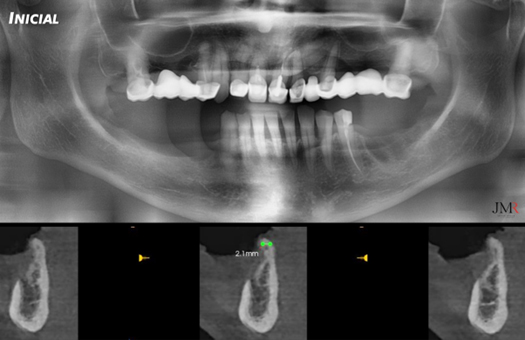

Figura 1.

Pruebas radiográficas iniciales: Radiografía panorámica y CBCT (plano sagital), donde observamos el grado de atrofia ósea horizontal (moderada – severa) del defecto y su relación con el agujero mentoniano.